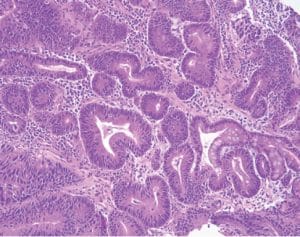

From the chapter “Genetic tumour syndromes of the digestive system,” juvenile polyposis syndrome.